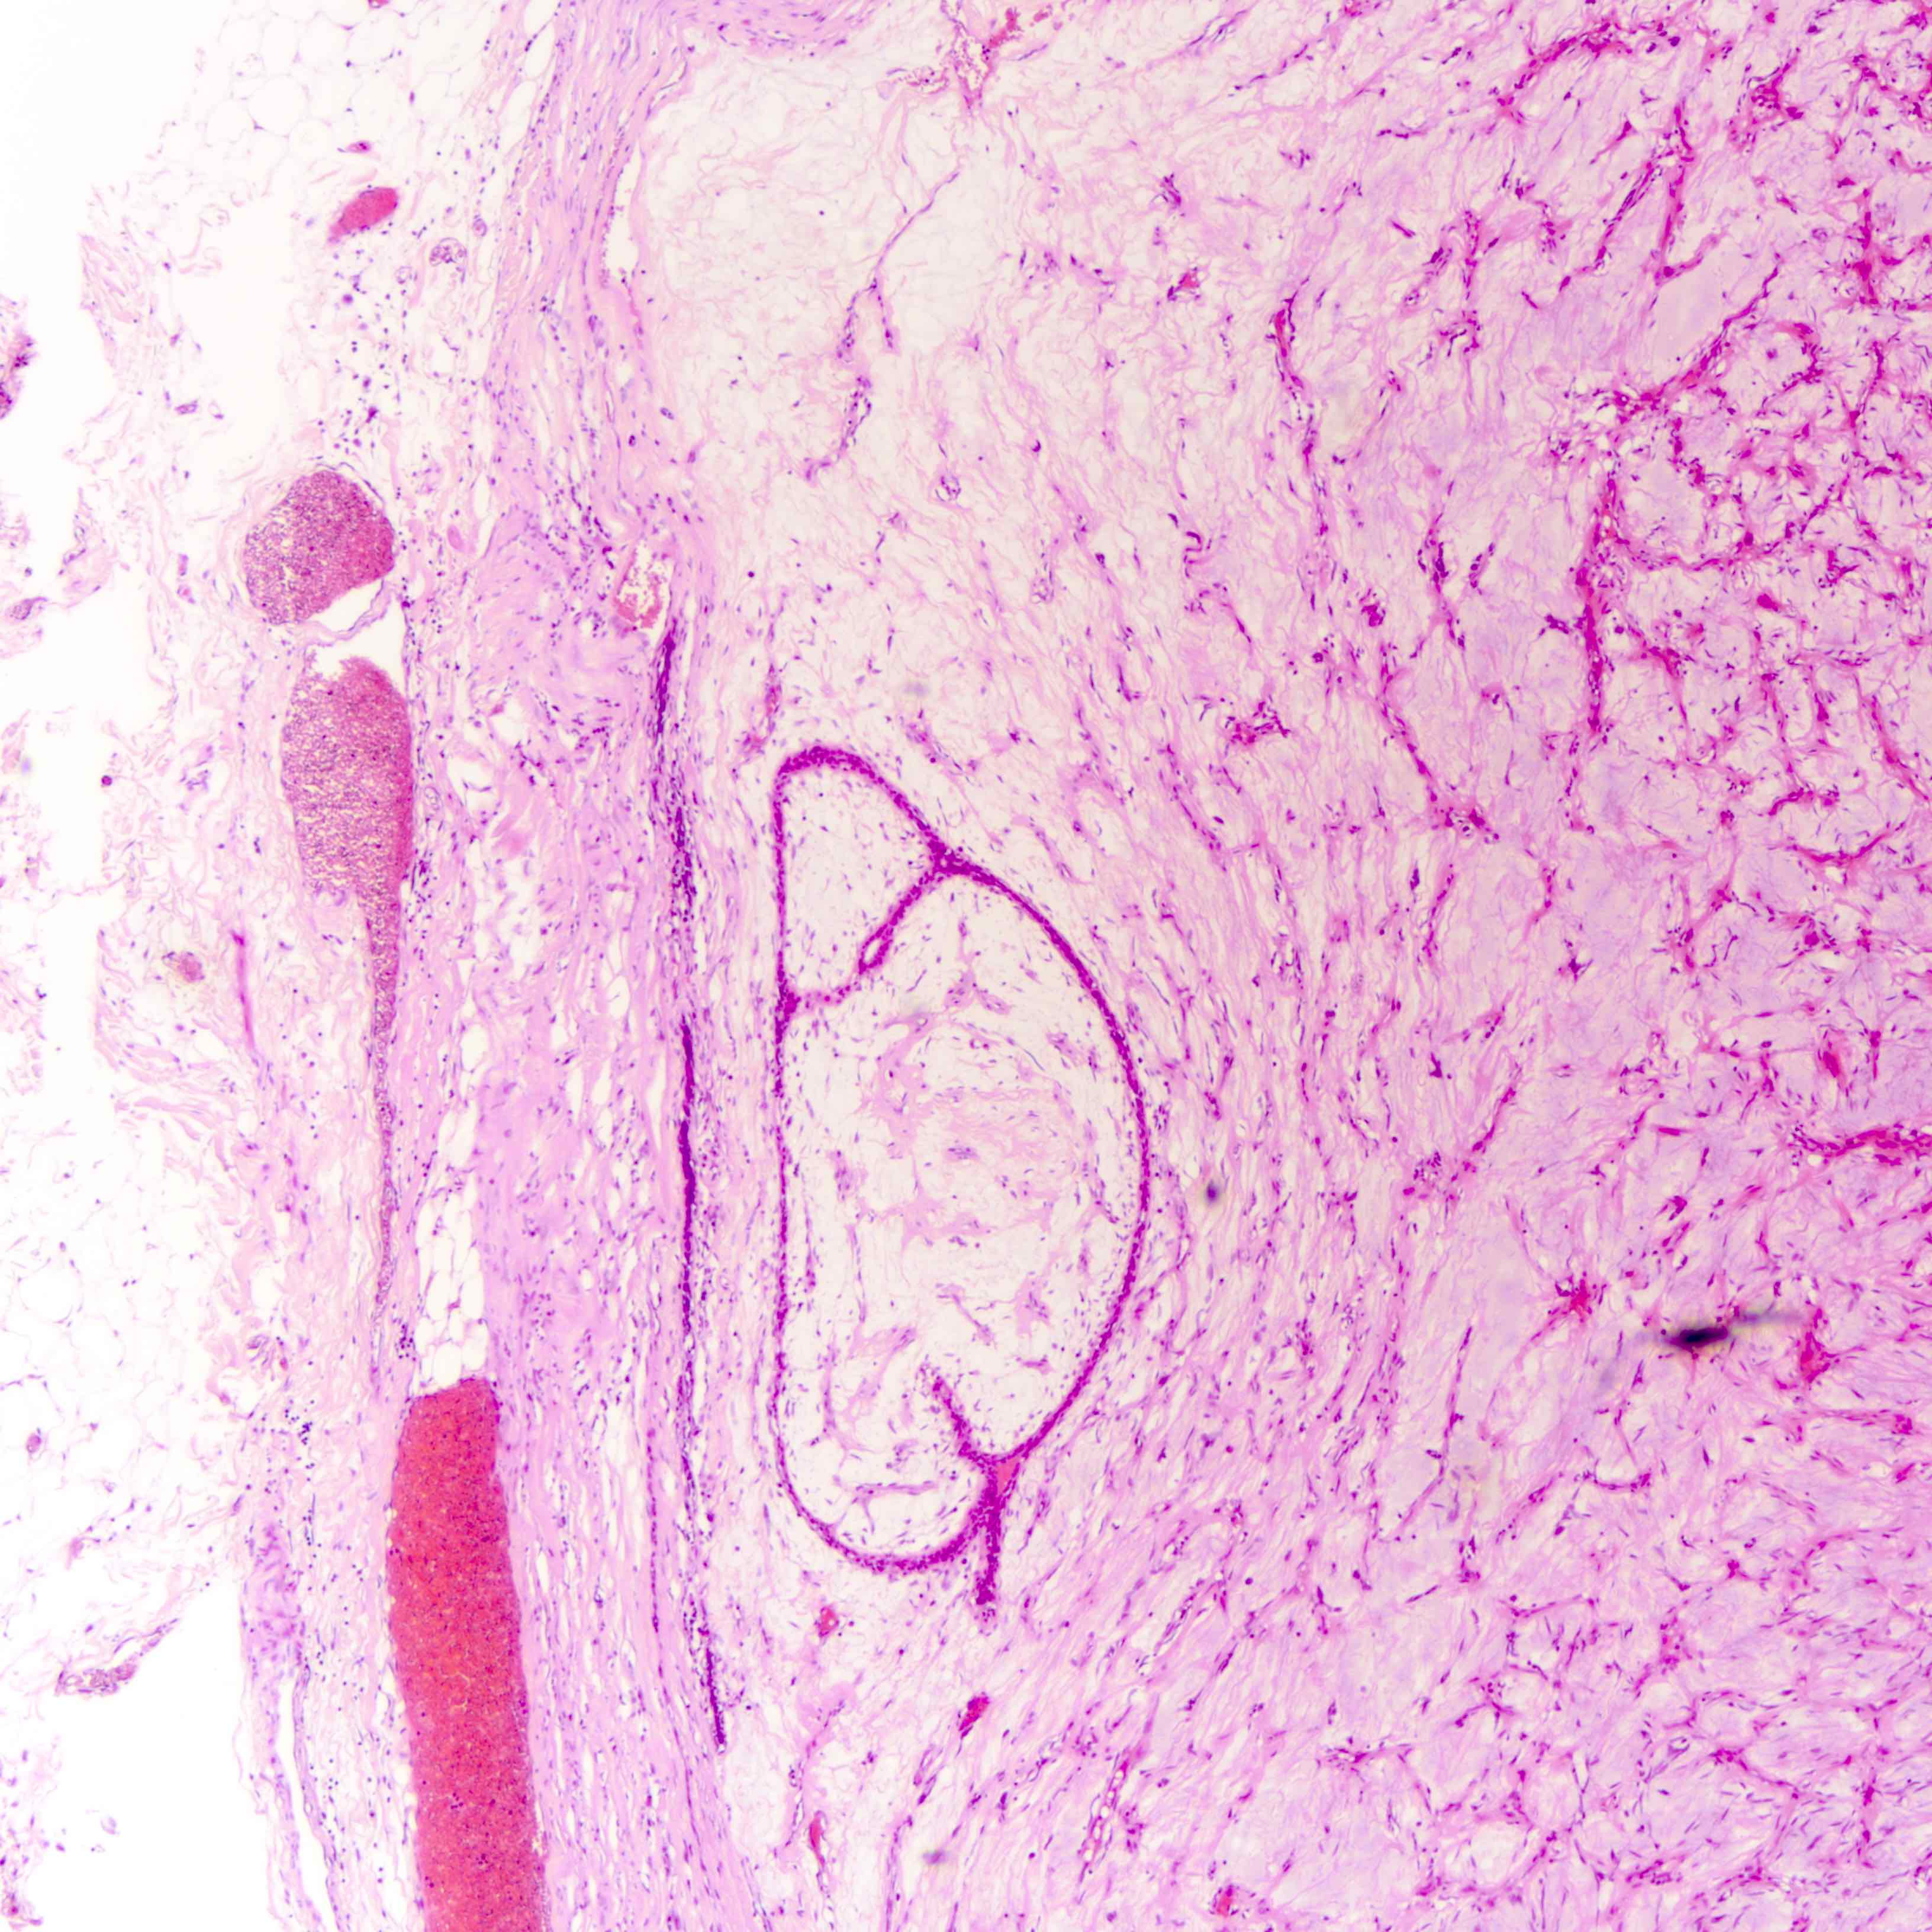

Microscopic (histologic) images

Contributed by Joshua J.X. Li, M.B.Ch.B. and Gary M. Tse, M.B.B.S.

Malignant phyllodes tumor